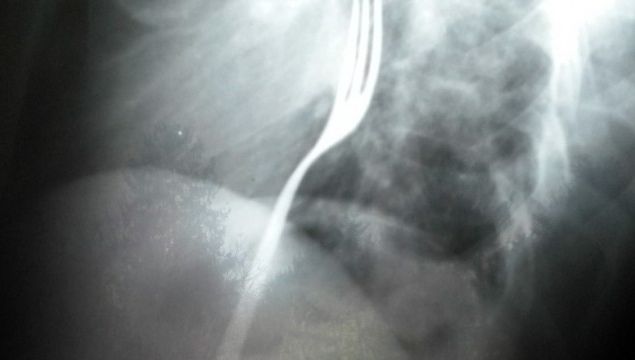

În noaptea de luni spre marţi, la Unitatea de Primiri Urgenţe a Spitalului Judeţean Bacău a ajuns un tânăr, în vârstă de 28 de ani, şi a cerut ajutorul medicilor pentru că înghiţise o furculiţă.

I s-a efectuat o radiografie, iar pe film s-a putut vedea furculita, pe care o ingerase cu coada in jos, blocata in esofag, scrie desteptarea.ro.

Individul a fost internat in Sectia de Chirurgie si se afla sub supravegherea medicilor de aici. Cel mai probabil el va fi supus unei interventii chirurgicale in momentul in care obiectul va ajunge in stomac, asta daca nu va fi eliminata pe cale naturala.